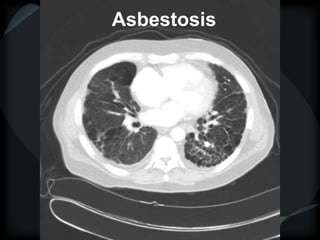

RETICULAR PATTERN - UIP

 peripheral reticular lines / inter and intralobular septae

 honeycomb

 Traction bronchiectasis

 None or minimal ground glass

 Gradient increasing from apex to base

 Asbestosis = basilar – bands – pleural calcification

Asbestosis